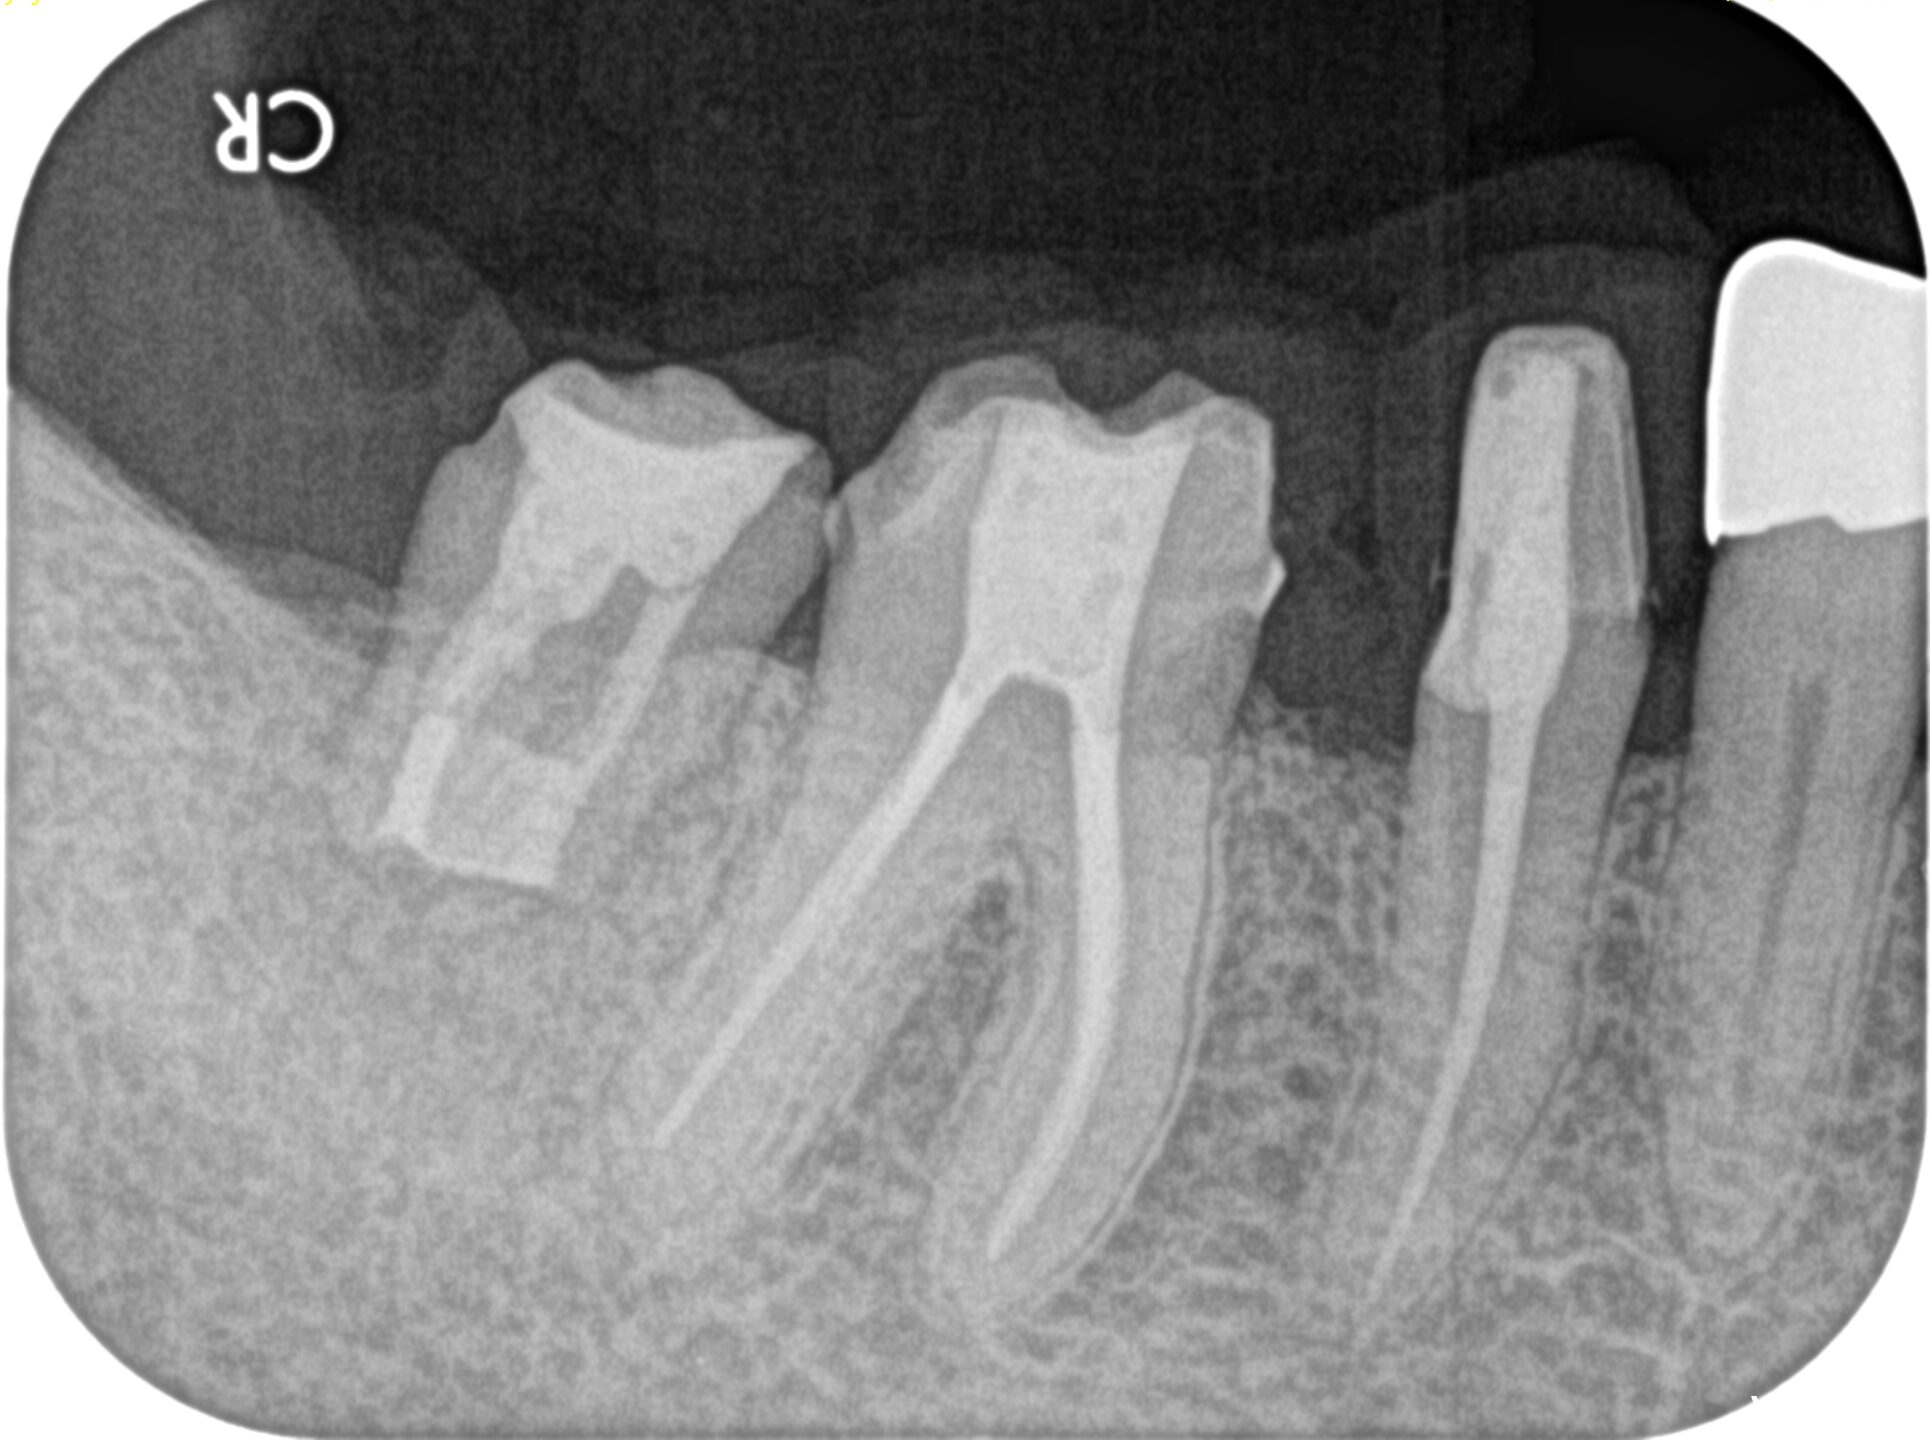

PA(2025.5.19)

確かに…

折れていると言われかねない状況だ。